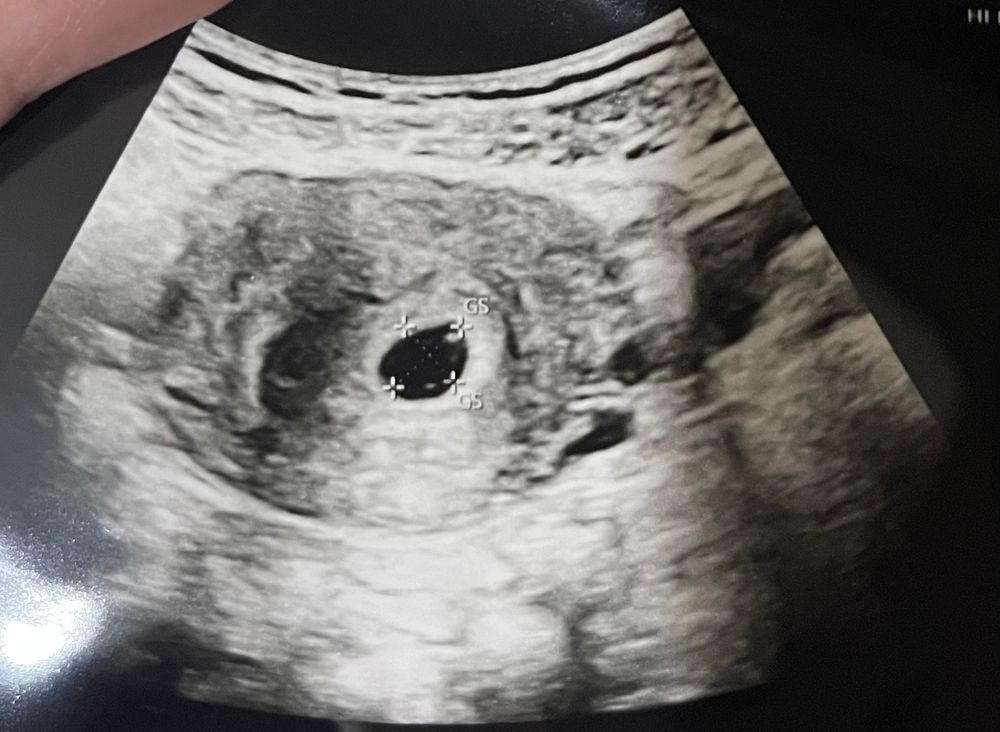

Была на узи, очень быстро, врач сказала срок 5+5

пя 10мм, жм есть, эмбриона пока не видно, приходите через неделю;

Смотрю на фото и не понимаю, где тут жм? чтото он вообще не похож на колечко, точка какая то, Может не туда смотрю или он какой то неправильной формы у меня?

Просто срок ещё маленький. Все хорошо у вас. Я примерно на таком же сроке 1 узи делала и колечка у меня не было, а просто пульсирующая точечка) Можете в дневнике у меня посмотреть